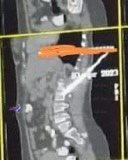

من جانبها، قالت الدكتور منال المصر،ي عميدة كلية طب قصر العيني ورئيس مجلس إدارة مستشفيات جامعة القاهرة، إن العملية الجراحية التي تم إجراؤها كانت على جانب كبير من الخطورة خوفًا من دخول السكين في أحد الشرايين الأساسية أو الحبل الشوكي أو الأمعاء، وتم عمل الإجراءات الطبية اللازمة بشكل سريع قبل إجراء الجراحة مثل الأشعات المقطعية، وحجز أكياس الدم والبلازما اللازمة، وتم إجراء العملية الجراحية بمهارة كبيرة أسفرت عن استقرار حالة المريضة.